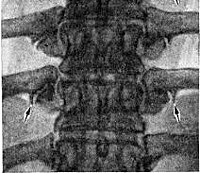

M47 Спондилез